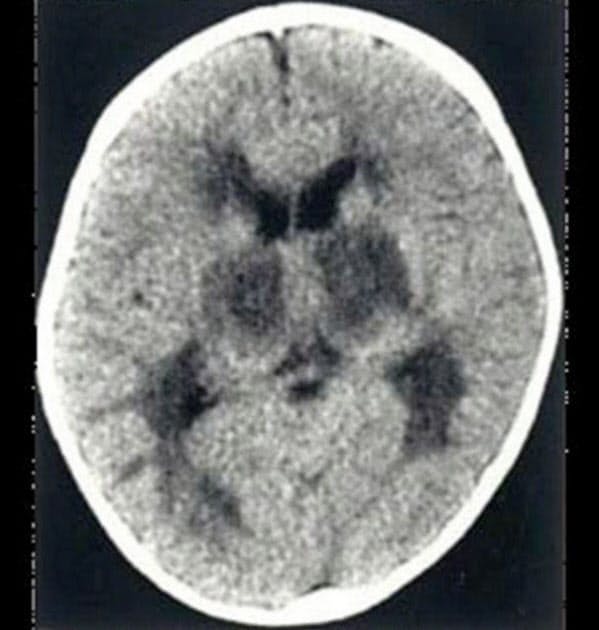

インフルエンザ 脳症 死亡 子供

発熱翌日に死亡 インフルエンザ脳症の怖ろしさ 小児の解熱剤や総合感冒薬服用は要注意

インフルエンザ脳症 既に34例 2歳児と5歳児が死亡 日経メディカル

インフルエンザ脳症で3歳児と8歳児が死亡 日経メディカル